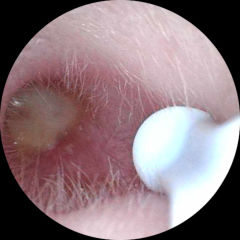

bananaphon · 05/07/2024 07:36

Update pics! The last one was taken this morning. My ear drum is no longer blocked which is such a relief. This was just by using olive oil drops on the 2 occasions and the wax has slowly softened and come out in the last week. Since last night and I can actually hear properly for the first time since May!

Used my ear camera

OP posts: